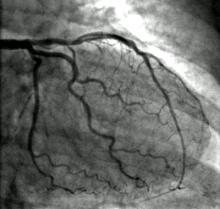

March 17, 2010 – Body size, gender and the complexity of heart disease significantly influence how much cumulative radiation skin dose patients receive during percutaneous coronary intervention (PCI) therapy, according to a new Mayo Clinic study. The study was undertaken as a quality control initiative to reduce the potential radiation risks of cancer to patients and PCI operators.